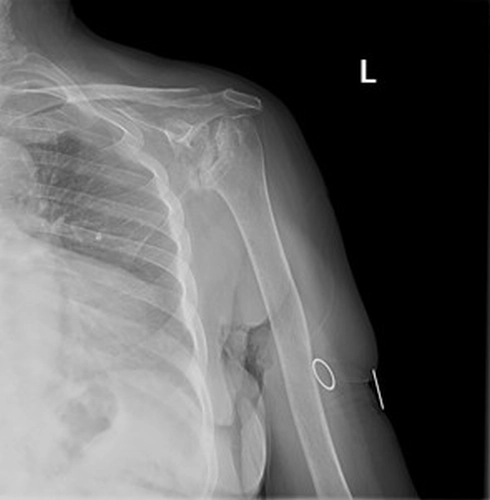

Sol Omuz MRG: Glenoidde kortikal düzensizlikler, lokalize defektif alanlar ve bu düzeyde subkondral milimetrik kistlerin eşlik ettiği medüller hafif hiperintens ödem izlenmektedir. Humerus baş kesiminde medialde de geniş bir alanda defektif görünüm mevcuttur. Buna komşu humerus başında milimetrik kistler ve medüller ödem izlenmektedir.

Humerus başında ve glenoid de osteofitik dejeneratif değişiklikler mevcuttur. Gleno-humeral eklem aralığı anterior inferiorda daralmıştır.Eklem aralığında sıvı miktarında belirgin artış izlenmedi.

Humerusta tüberkülüm majusta milimetrik kist - medüller ödem benzeri sinyal değişikliği dikkati çekmektedir.

Akromioklaviküler eklemde minimal dejeneratif hipertrofi izlenmekte olup eklem aralığı yaklaşık 5 mm ölçülmüştür ve normal sınırlar içerisindedir. Subakromial yağ mesafesi basılıdır. Akromion Tip 2 konfigürasyondadır. Glenoid labrumlar değerlendirilemedi. Biceps uzun başı tendonu normaldir. Supraspinatus tendonunda tendinozis izlenmektedir.

Ön tanıda romatoid artrite bağlı eklem tutulumu, avasküler nekroz, Charcot eklemi (periferik nöropati- servikal radikülopati?) olasılıkları tartışıldı. Hastanın ileri derecedeki eklem kısıtlılığı ve buna bağlı gelişen omuz çevresi kaslarda atrofisi olması sebebi ile artroplastiden fayda görebileceği öngörüldü.